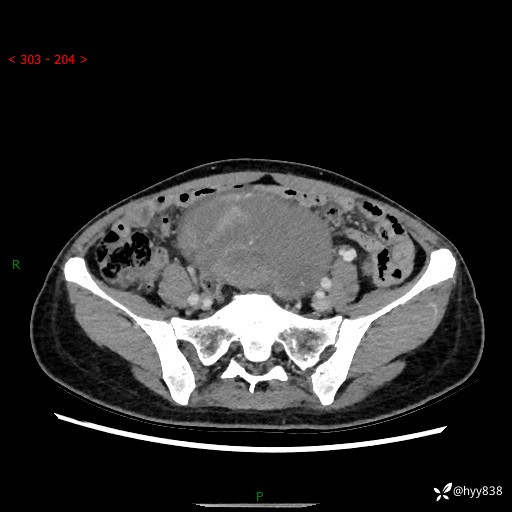

【患者信息】:女,50岁

【主诉】:外院超声发现腹盆肿块,为进一步诊治来我院,门诊已“盆腔肿块”收入院。

腹盆CT平扫+增强

【临床诊断】:盆腔肿瘤